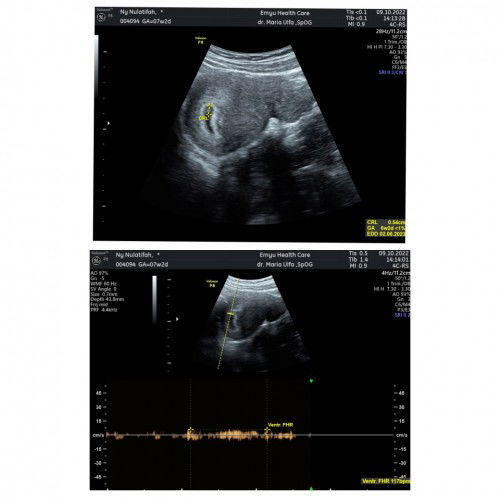

Usia kandungan

Bun , itu sebenernya usia kandungan berapa ya bun , di usg sama detak jantung beda bun , kasih informasinya bun